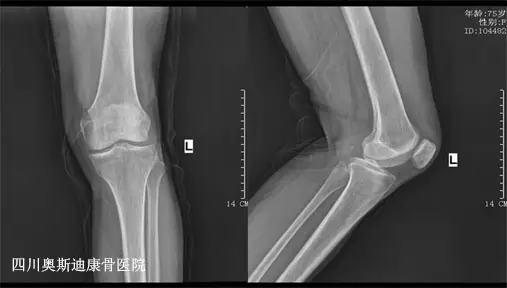

75岁的黄女士在半年前出现左膝及左髋关节疼痛,下蹲后站起来都很困难,平时上下楼梯都很吃力,特别是在阴雨天行走的时候疼痛感更加加重了,这病情令黄女士非常的苦恼,因此,黄女士便来到我院接受治疗。

我院专家组介绍到,骨性关节炎是一种常见的慢性关节疾病,其主要病变是关节软骨的退行性变和继发性骨质增生,多见于中老年人,女性多于男性,好发在负重较大的膝关节、髋关节、脊柱及手指关节等部位。骨性关节炎的关节痛多出现在负重关节如膝、髋等;关节痛与活动有关,在休息后痛就缓解;在关节静止久后再活动,局部出现短暂的僵硬感,持续时间不超过30分钟,活动后消失;病情严重者即使在休息时都有关节痛和活动的受限;受累关节往往伴有压痛、骨性肥大、骨性摩擦音、少数患者有畸形。

针对黄女士的病情,我院专家组采用小针刀配合玻璃酸钠关节腔灌注,配合针灸、推拿、中药外用等治疗,目前黄女士的病情有所好转。